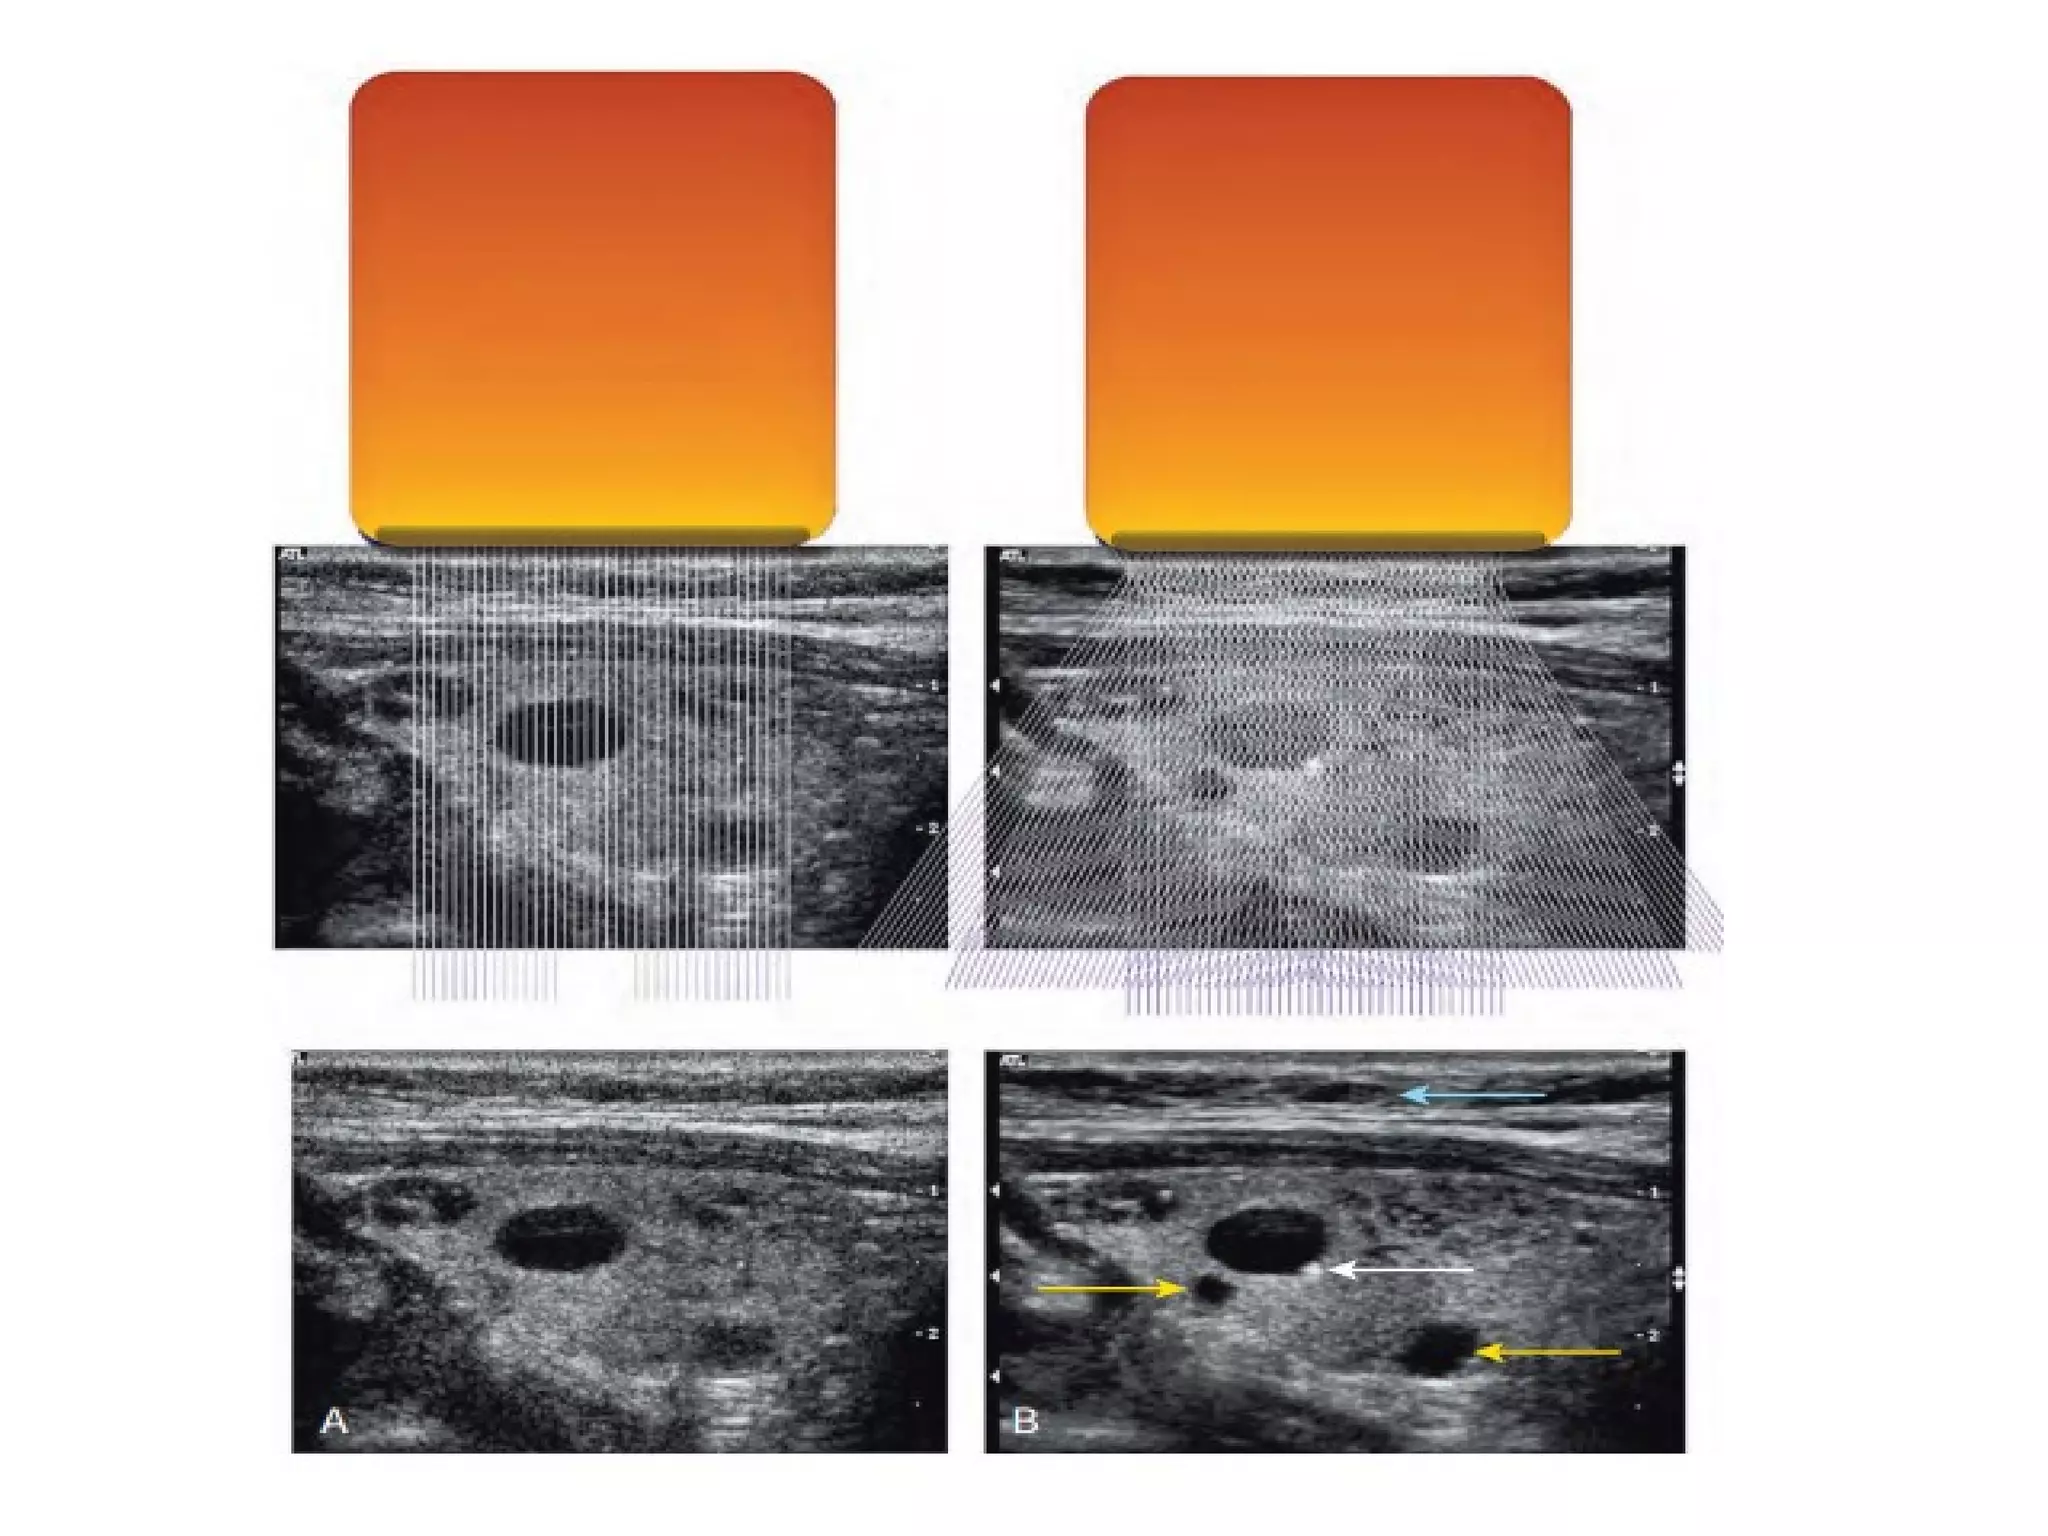

Spatial Compound Imaging

• An important source of image degradation and

loss of contrast is ultrasound speckle.

• Speckle results from the constructive and

destructive interaction of the acoustic fields

generated by the scattering of ultrasound

from small tissue reflectors.

• This interference pattern gives ultrasound

images their characteristic grainy appearance

reducing contrast and making the identification

of subtle features more difficult.

• in spatial compound sonography information is

obtained from several different angles of

insonation which are combined to produce a single

image .

• This is unlike conventional B-mode sonography, in

which each image is obtained from a single angle of

insonation.

• By averaging images from multiple angles of

insonation, SCI has been shown to reduce many

image artifacts inherent in conventional sonography.

• Application of SCI has been described in imaging of

breast, peripheral vessels, and musculoskeletal

system. It can also be combined with other

ultrasound applications, e.g. harmonic imaging.